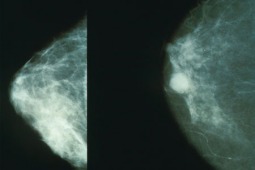

Rośnie liczba pacjentek w mammobusach na Mazowszu

Niemal 130 tys. przebadanych kobiet i bez mała 1200 postojów mammobusów to tegoroczny bilans „Populacyjnego Programu Wczesnego Wykrywania Raka Piersi” na Mazowszu.